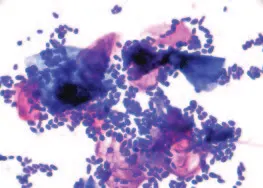

Yeast: Malassezia pachydermatis is the most common budding organism found in canine ears. This yeast is typically peanut-shaped, with a size ranging from 3 to 5 mcm. These organisms are often clustered around keratinocytes (Figure 3).

Malassezia yeast organisms (too numerous to count) clustered around keratinocytes (modified Wright’s stain; original magnification, 100´; immersion oil).